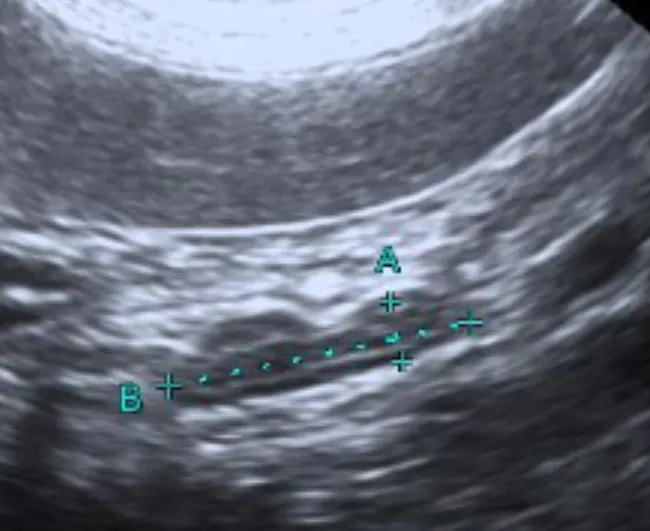

➡️腹腔超音波區別腎上腺的型態:超音波可以分辨腎上腺的對稱性,通常PDH兩邊的腎上腺是對稱的。如果是腎上腺腫瘤,會失去內部正常的結構,另一側的腎上腺也會比較小(腎上腺高度會小於0.4-0.5cm),

通常腎上腺腫瘤是單側的,但也有可能出現雙側。腎上腺腫瘤跟巨型節結性增生 (micronodular hyperplasia) 難用影像區分,但一般腎上腺高度如果大於四公分則通常是惡性的。腎上腺腫瘤會侵入後腔靜脈,轉移到腹腔其他器官或是胸腔。

正常的腎上腺型態

腫大的腎上腺型態